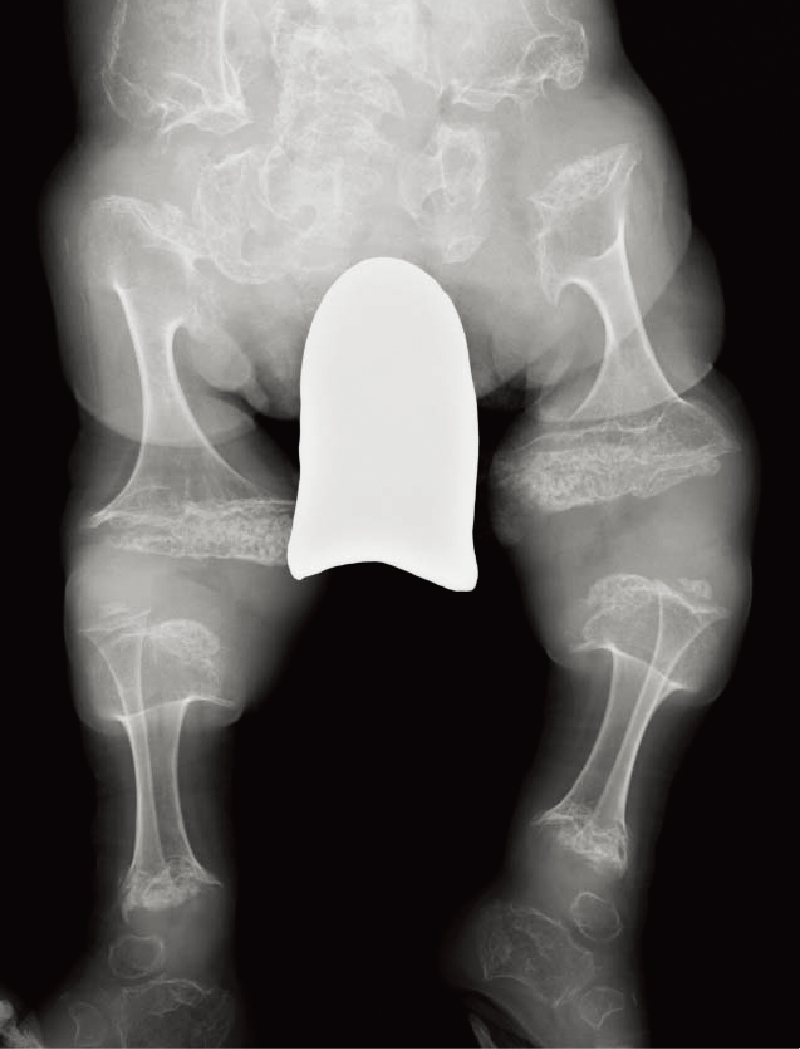

整形外科的臨床所見/特異顔貌および眼・耳などの合併症など:特異顔貌(卵型で平坦な顔、青色強膜、眼球突出など)を呈する。皮膚は柔らかく、筋緊張は低下する。進行性の脊柱変形があり(A)、下肢アライメント異常を呈することがある(B)。

A. 全脊柱正面像(11歳、女):著明な脊柱側弯を認める。

B. 両下肢正面像(7歳、女):軽度の外反膝と骨端不整を認める。